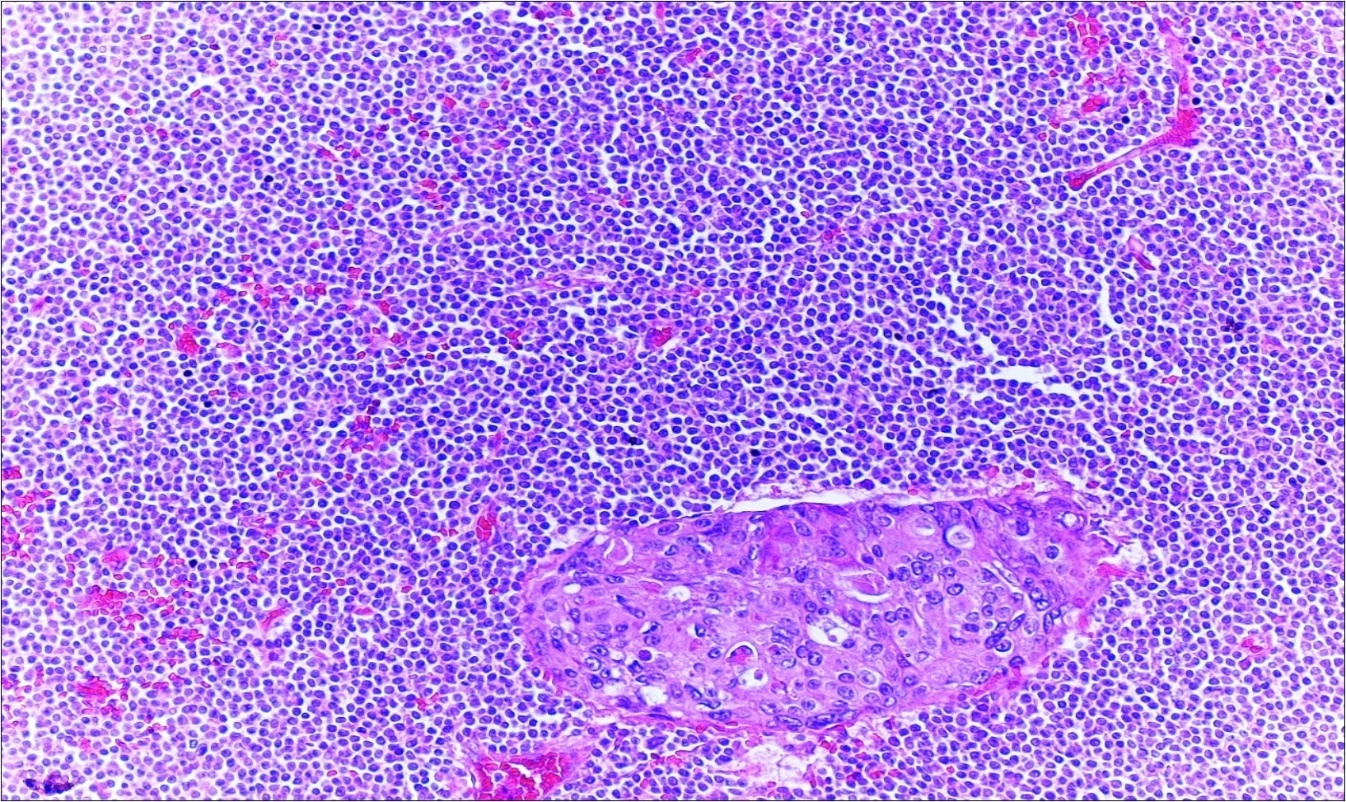

A 63-year-old woman presented to the Department of General Surgery as an outpatient with abdominal pain. Physical examination showed the signs of acute appendicitis and appendectomy was performed. During microscopic examination, a small focus of atypical monotonous lymphoid cell population was seen and the material was sampled totally. The pathological examination revealed MALT lymphoma (Figure 1), with diffuse positivity of cluster of differentiation (CD) 20 (Figure 2), CD 79a and B-cell lymphoma (Bcl- 2) (Figure 3) with just a few CD3 positive lymphoid cells. However, no evidence of adenocarcinoma was found in the appendectomy specimen. After the diagnosis of lymphoma, a complete colonoscopy was planned and this revealed a solid tumoral mass in the caecum measuring 5x4x4 cm. Computed tomography of the abdomen and pelvis revealed mesenteric lymphadenopathy associated with a mass in the caecum with multiple nodules in liver consistent with metastasis (Figure 4). Frozen sections were not obtained since the treatment method would not be affected. The patient underwent anterior resection with regional lymphadenectomy, with the pathological assessment of the resected specimen revealing a collision tumor consisting of a poorly differentiated adenocarcinoma extending through the muscularis propria with MALT lymphoma (Figure 5). Microscopic evaluation of the 11 regional lymph nodes in the mesentery of the resected colon and liver biopsy showed diffuse infiltration of MALT lymphoma with metastasis of adenocarcinoma (Figure 6). According to immunohistochemistry, atypical lymphocytes were positive for CD 20, Bcl-2, and negative for CD3, CD5, CD10, CD23, Bcl-6, terminal deoxynucleotidyl transferase, and cyclin D1. The proliferation fraction (MIB-1 immunostaining) was approximately 20%. The morphological and immunohistochemical findings were used to confirm the diagnosis of synchronous presentation of MALT lymphoma and colon adenocarcinoma within the caecum, mesenteric lymph nodes and liver metastases.

Figure 6.Adenocarcinoma with MALT lymphoma infiltration of lymph node (h&e;200)

Adenocarcinoma with MALT lymphoma infiltration of lymph node (h&e;200)